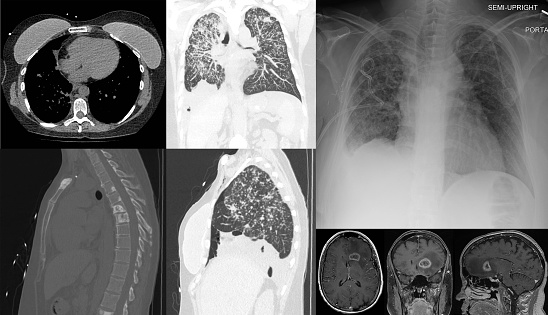

전이성 유방암 진단은 초기 유방암과는 다르게, 이미 암이 다른 장기로 퍼진 상태이기 때문에 더 철저하고 다양한 검사 방법이 필요해요. CT, MRI, PET-CT와 같은 첨단 영상 진단 기술을 이용하여 전이된 암의 위치와 크기, 그리고 암세포의 특성을 파악하는 것이 중요해요.

이러한 정보들은 치료 계획을 세우는 데 있어서 매우 중요한 기초 자료가 되죠. 정확한 진단은 최적의 치료 방법을 결정짓는 첫걸음이며, 환자의 생존율 향상에 결정적인 요소가 되는 만큼, 정밀한 진단 절차에 대해 이해하고, 적극적으로 참여하는 것이 매우 중요하답니다.